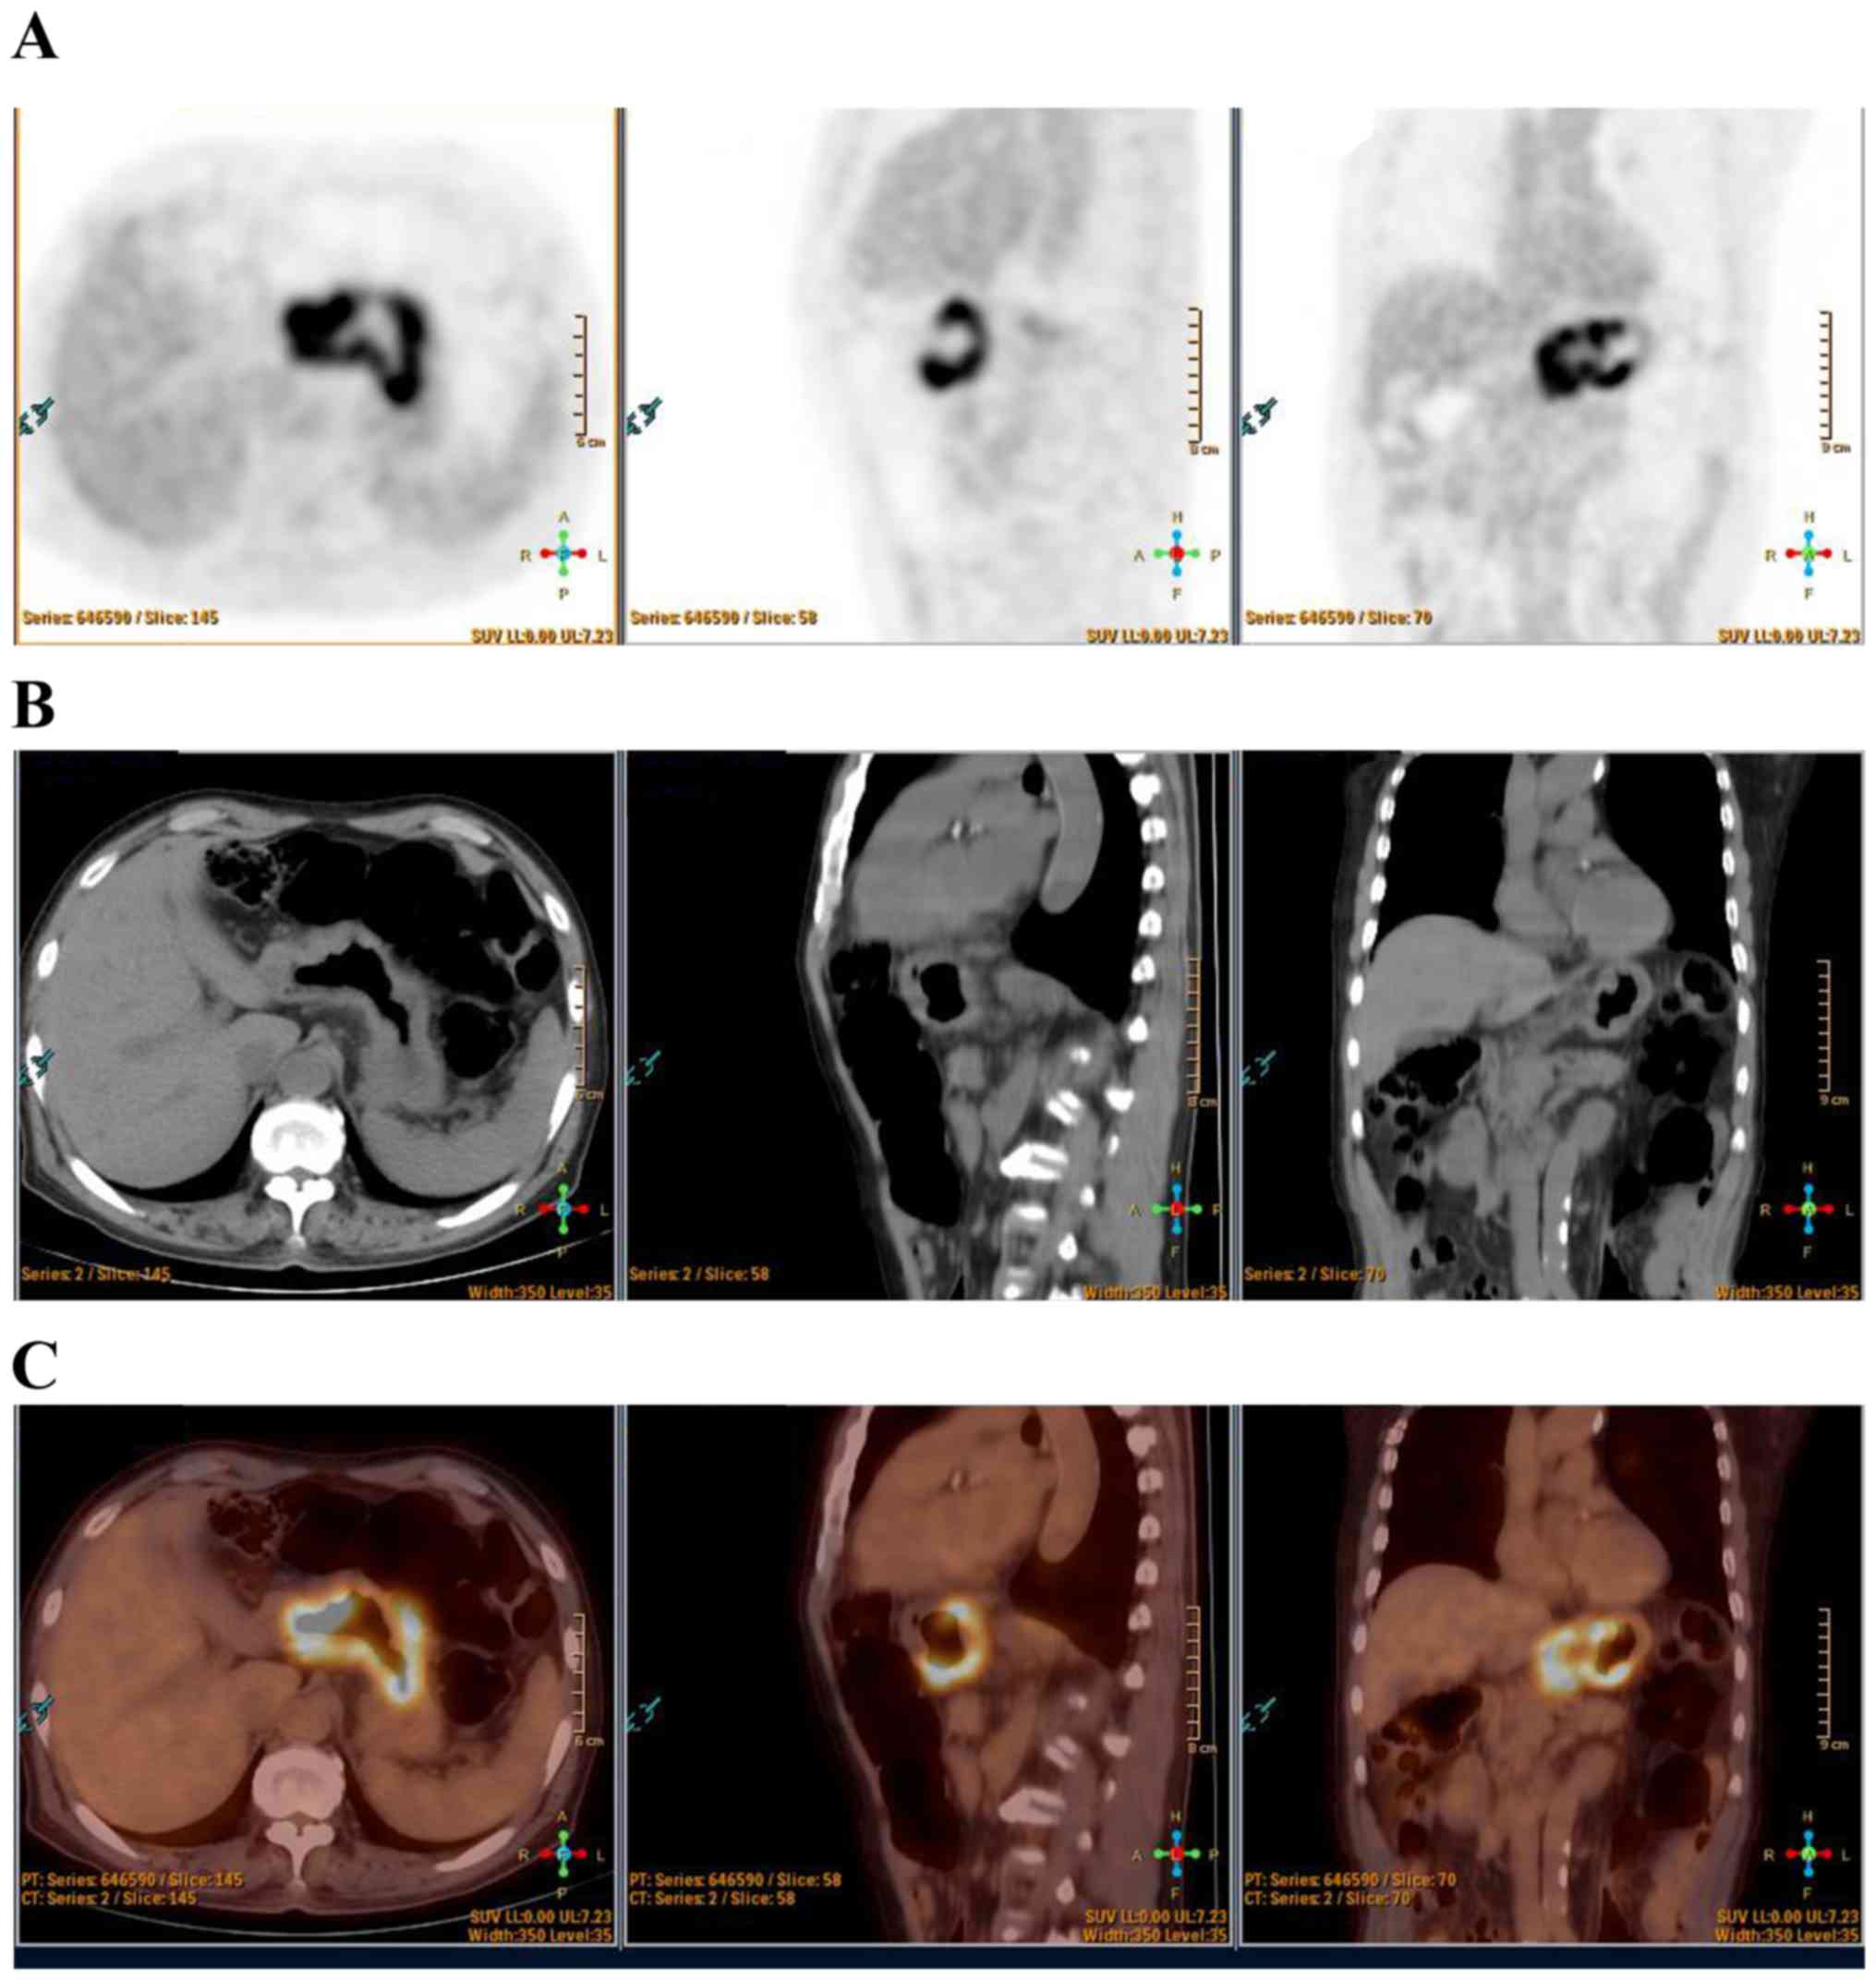

A 55 Year Old Male With Gastric Cancer Identified By Fdg Pet Ct A Download Scientific Diagram

A C A 53 Year Old Women With Stomach Cancer Underwent Fdg Pet Ct The Download Scientific Diagram